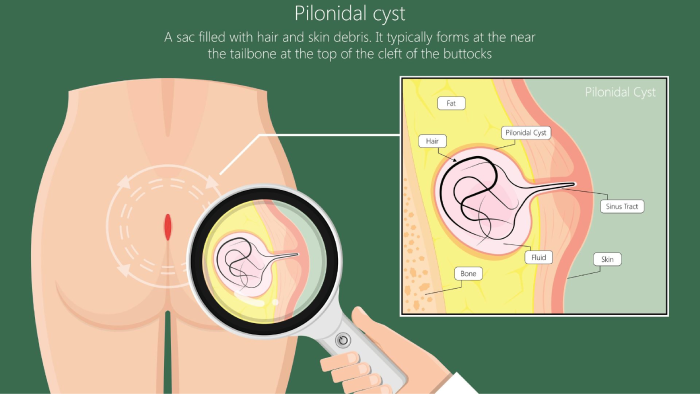

۵. کیست پیلونیدال

کیست پیلونیدال تودهای کوچک و دردناک در بالای خط باسن است که معمولا در اثر برگشت مو به زیر پوست به وجود میآید. این کیست میتواند عفونی و پر از چرک شود و باعث التهاب و درد در ناحیه نزدیک دنبالچه گردد. بیماران معمولا از تورم، قرمزی یا ترشح چرکی در ناحیه شکایت دارند. در چنین شرایطی، منبع اصلی درد خود دنبالچه نیست بلکه التهاب ناشی از کیست است.